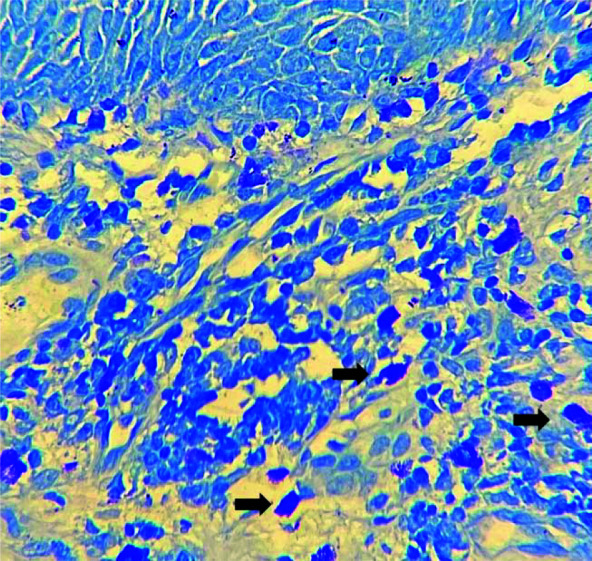

Materials and method: In this retrospective cross-sectional study, sixty-three archival cases, including 22 OSCCs, 28 dysplastic leukoplakias as epithelial dysplasia (ED), and 13 normal oral mucosal tissues, were examined for mast cells, using toluidine blue staining. Hotspot areas were identified at 10× magnification and mast cells were counted in 5 fields at 40× magnification. The average cell numbers were calculated, and the severity of inflammation was scored. Statistical analysis was performed using SPSS statistical software 20, including One-way ANOVA, Two-way ANOVA, paired-t test, and independent t-test. p Value < 0.05 was considered significant.

Results: Among the 51 pathologic lesions, 54.9% were males and 45.1% were females, with a mean age of 56.34±15.35 years. The most common locations were the tongue and buccal mucosa. The mast cell count was significantly lower in SCC compared to ED (p= 0.009). There was no correlation between mast cell count and inflammation score (p= 0.345).

Conclusion: In this study, the mast cell count was higher in ED compared to OSCC, suggesting an increase in these cells during the pre-malignant stages. However, the number of mast cells decreased after connective tissue invasion and microenvironmental changes occurred.